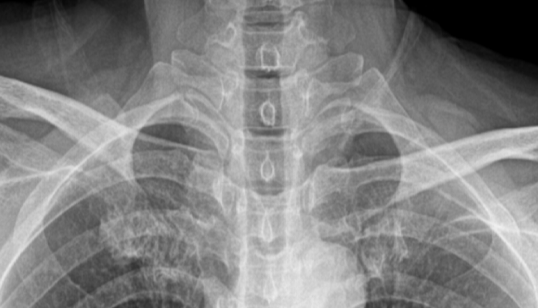

头颈正位片

灰阶对比突出,细节丰富